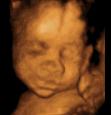

四维彩超能看到宝宝在肚子里的动作和表情,想把彩超的图像作为宝宝人生的第一张照片来收藏,首选四维彩超~

麻麻,我有点累了,换个姿势~

在妈妈肚子里最舒服了,我睡的很香哦!

宝宝在妈妈肚子里真的是生活的多姿多彩呢!